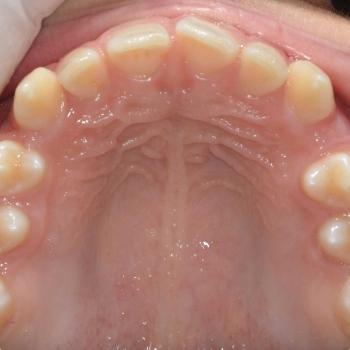

A kezelési terv természetesen az összes eltérést figyelembe vette és ennek megfelelően a problémák megoldásához rögzített fogszabályozót, EVA-platte harapásemelőt és különböző intermaxilláris gumikat használtunk.